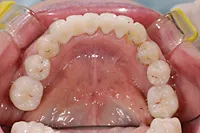

矯正及びインプラントで治療のケース

■治療前1

■治療後1

■治療前2

■治療後2

■治療前3

矯正により歯の位置を適正な位置に動かし、歯の無い部分に対してインプラントにより回復したケースです。

■治療後3

上下とも美しい歯並びと噛み合わせになりました。 形だけでなく、色みも自然な仕上がりです。

| 主訴 | 下の歯が1本無いので歯ならびが良くなく、かみ合わせも悪い |

|---|---|

| 治療方法 | 矯正治療+インプラント治療+補綴治療 |

| 治療期間 | 約3年 |

| 通院回数等 | 約35回 |

| 費用 | 約160万円 |

| リスク・副作用 | 矯正治療も行ったので治療期間が長くなった インプラント術後の腫れ・痛み |